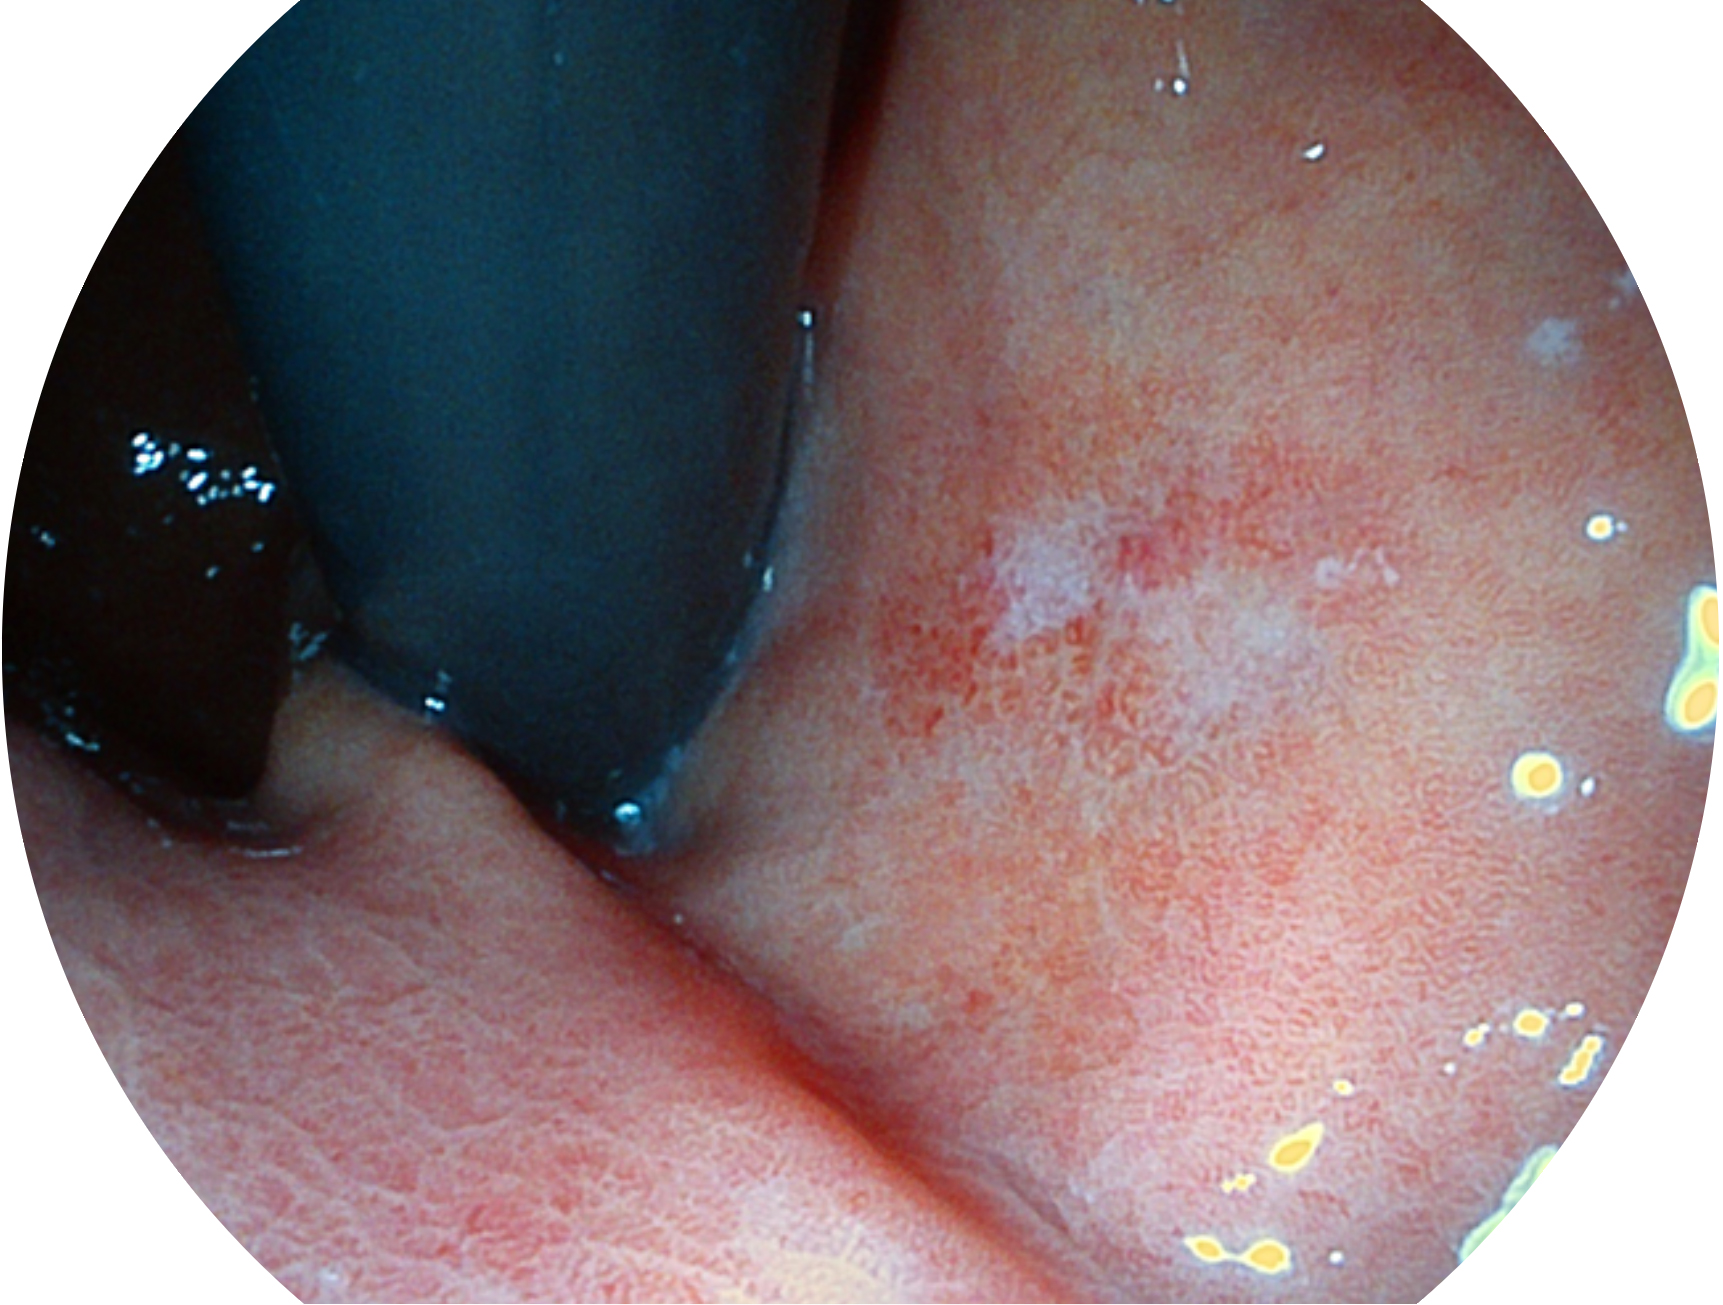

与上一代VIST相比,摒弃了滤光转轮而直接采用光谱组合的方案,加入了血红蛋白吸收高峰与次高峰的蓝紫光和绿光光谱,更有利于黏膜血管吸收,突显浅表层血管和中层血管的对比度,因而具备更高的图像对比度,近景观察时,有助于微细结构变化及病灶边界的观察。

• 白光图像 VIST图像